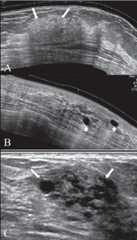

Ultrasound findings of fibrocystic change:

Extended view images (A, B) show a focal area of thickening of the breast parenchyma (A) with patchy increase in echogenicity (arrows) and scattered, discrete, thin-walled cysts (arrowheads in B). The “lump” may shows a combination of clustered tiny cysts and thickened parenchyma (arrows in C).